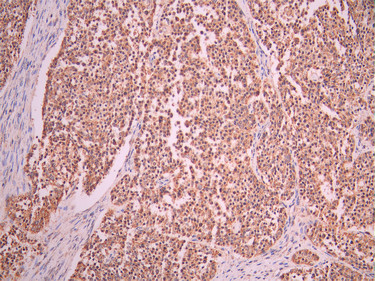

• IHC image of CSB-RA283972A0HU diluted at 1:100 and staining in paraffin-embedded human liver cancer performed on a Leica BondTM system. After dewaxing and hydration, antigen retrieval was mediated by high pressure in a citrate buffer (pH 6.0). Section was blocked with 10% normal goat serum 30min at RT. Then primary antibody (1% BSA) was incubated at 4°C overnight. The primary is detected by a Goat anti-rabbit polymer IgG labeled by HRP and visualized using 0.05% DAB.